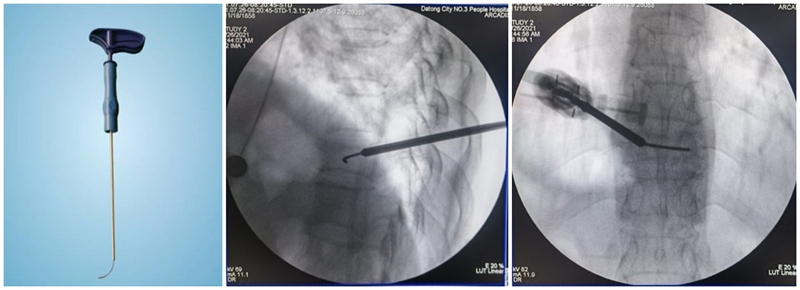

(3)弯角骨钻扩张:C形臂X线机正位透视下,弯角骨钻开腔器械螺旋手柄顺时针扭转,让弯角骨钻沿导丝前进开路,将椎体内部钻出弧形通道。操作中注意骨钻沿导丝旋进旋出要完全,旋进不够,后期球囊无法到达对侧,旋出不完全,骨钻会卡在工作套筒上无法拔出。

(4)置入球囊:插入带导丝弯角球囊时注意透视球囊方向,反复调整务必与终板平行。如需要拔出球囊调整方向,务必先拔导丝再拔球囊,透视球囊标记点必须完全从工作套管内出来,否则易造成弯角球囊与工作套管边缘卡磨破裂。

(5)扩张球囊:注入造影剂扩张球囊过程中,注意观察术中正侧位透视图像,控制压力值,不必苛求球囊顶到上下终板,以免发生医源性终板破裂,造成椎间隙骨水泥渗漏可能。注意弯角球囊扩张完毕后拔除顺序:先拔导丝再拔球囊。